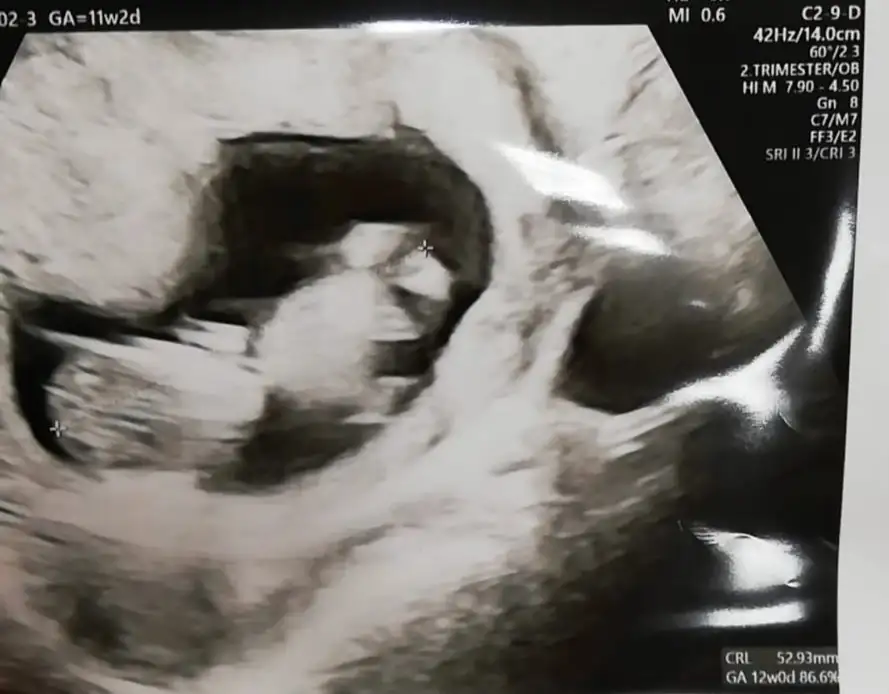

Çok fazla görünmüyor bebişKızlar merhaba, kontrolden çıktım 11+2 haftalığız cinsiyet bi sonrakine dedi. Sizin tahmininiz var mı çok merak ediyorum :)